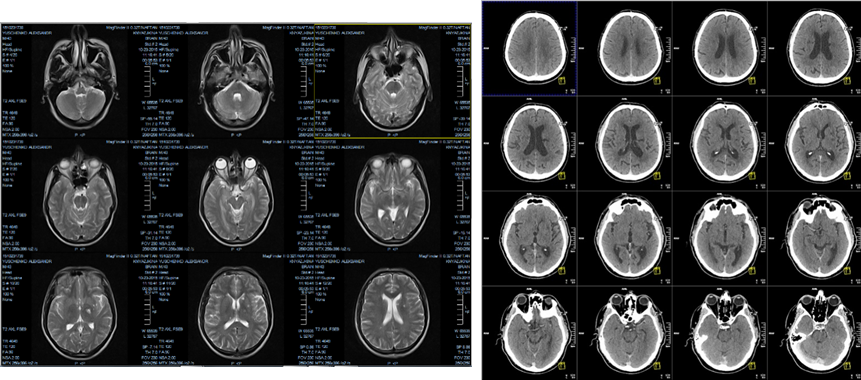

Так, каждое исследование представляет собой набор 2D-изображений – слайсов, привязанных к реальным пространственным координатам. Каждый слайс представляет собой прямоугольный параллелепипед, у которого одна сторона (толщина) намного меньше двух других. Да, несмотря на 2D-представление слайса, он визуализирует часть 3D-пространства – об этом будет подробнее рассказано далее.

Слайсы располагаются дискретно. Толщина и расстояние между центрами соседних слайсов являются важными характеристиками данных. Если толщина меньше расстояния, то между слайсами образуются зазоры. Если больше, то слайсы содержат информацию из перекрывающихся областей.

Компьютерная обработка исследований может осуществляться в 2D, когда используется каждый слайс как независимое от остальных изображение. А можно собрать слайсы в «стопку» и обрабатывать уже 3D-методами. Кроме того, сегодня некоторые томографы позволяют формировать сразу 3D-данные, но не для всех настроек или с определенными ограничениями.

Еще один важный общий для всех томографий термин – проекция. Это плоскость, параллельно которой располагаются слайсы:

-

Ax, Axial, Tra, Transversal — аксиальная (трансверсальная) проекция;

-

Sag, Sagittal — сагиттальная проекция;

-

Cor, Coronal, Frontal — коронарная (фронтальная) проекция.

Наряду с прямыми проекциями, встречаются и «косые» (oblique), которые располагаются под разными углами.

Часто в рамках одного исследования формируется несколько наборов различных проекций. При отсутствии одной или двух они могут быть математически сформированы из имеющихся – с погрешностями, но достаточно наглядно для визуального анализа. Пригодность таких восстановленных проекций для обучения нейронных сетей стоит оценивать в зависимости от решаемой задачи и имеющегося набора данных.

1.3. Магнитно-резонансная томография

Магнитно-резонансная томография (МРТ) – это томографический метод исследования внутренних органов и тканей с использованием физического явления ядерного магнитного резонанса (ЯМР) атомов водорода под действием магнитного поля и радиоволнового излучения.

Из-за своей специфики МРТ применяют для исследования мягких тканей, например, диагностики травм мышц, сухожилий и хрящей, обнаружения и изучения опухолей, и т.п. Для изучения костных тканей МРТ плохо подходит.

По сравнению с КТ этот метод позволяет построить более контрастные и разнообразные изображения мягких тканей и, к тому же, без лучевой нагрузки на организм. В МРТ-данных вообще закодировано гораздо больше информации, чем в КТ. Но и сложностей с обработкой таких данных больше.